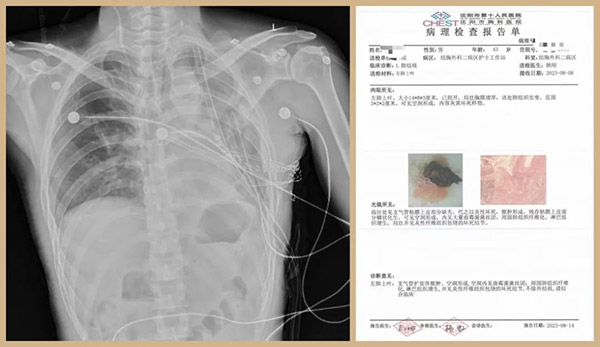

图为患者术后第二日床头胸部DR片和病理报告。

术后患者恢复良好,再无咳嗽、咳痰、咯血,萎靡状态一去不返,笑容再次挂在脸上,近日即可康复出院。面对疑难、复杂病例手术,考验的不仅仅是技术,还需要医者的勇气、信心、责任、担当和一心为患的情怀。